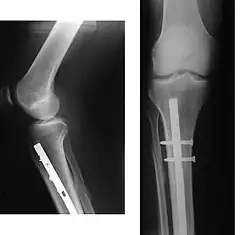

![]() | |

| Internal and external views of an arm with a compound fracture, both before and after surgery | |

A bone fracture (abbreviated FRX or Fx, Fx, or #) is a medical condition in which there is a partial or complete break in the continuity of any bone in the body. In more severe cases, the bone may be broken into several fragments, known as a comminuted fracture.[1] An open fracture (or compound fracture) is a bone fracture where the broken bone breaks through the skin.[2]